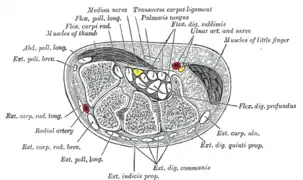

Transverse section across distal ends of radius and ulna. Transverse section across the wrist and digits.

Transverse section across the wrist and digits. Ulnar and radial arteries. Deep view.